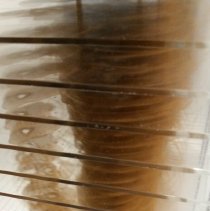

Bronze ink screen-printed on acrylic sheets, edition 4/6 |

Marilène Oliver (London, England 1977; lives and works in Alberta, Canada) Family Portrait (Mum and Dad), 2003 Bronze ink screen-printed on acrylic sheets, edition 4/6 75 1/2 x 27 1/2 x 19 5/8 inches Knoxville Museum of Art, 2015 purchase with funds provided by KMA Collectors Circle and partial gift of the artist British artist Marilène Oliver constructs provocative portraits of her family in the form of prints based on dozens of digital medical scans taken from head to toe. Family Portrait (Mum and Dad) was made by screen printing cross sectional MRI scans taken every inch onto sheets of clear acrylic and then stacking the sheets in order to construct an entirely new form of digital age portraiture. Oliver's interest in taking this approach was to explore "the notion of preservation and resurrection, and also to question the role/future of the body in an increasingly disembodied, digital age. By laying bare the mechanical digitization of the body on sheets of clear acrylic my aim was to expose the gaps, the loss, the trappings of the formal mechanisms but also the magic; the promise that we can be everywhere and nowhere, potentially anytime and forever." |